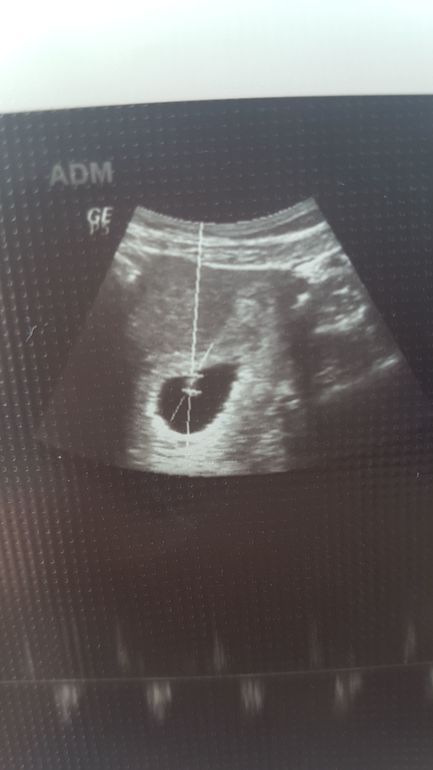

Болит живот и поясница, тонус, треникиДорогие девочки! Подскажите пожалуйста. Сделала узи в пятницу, сказали есть тонус. Вчера были бежевато - коричневые выделения, единоразово, 2 пятнышка на белье. Никаких болей. Не могу понять что это. Стала принимать папаверин + ношпа + магне б6. Сходила сегодня на узи, будучи обеспокоенной вчерашними выделениями. Тонуса нет, угрозы нет, в общем ничего нет. Подскажите пожалуйста, может было у кого то так же? И что за бежево-коричневые или очень светло коричневые выделения? Оба узи прикладываю, первое - в пятницу, второе - в воскресенье.